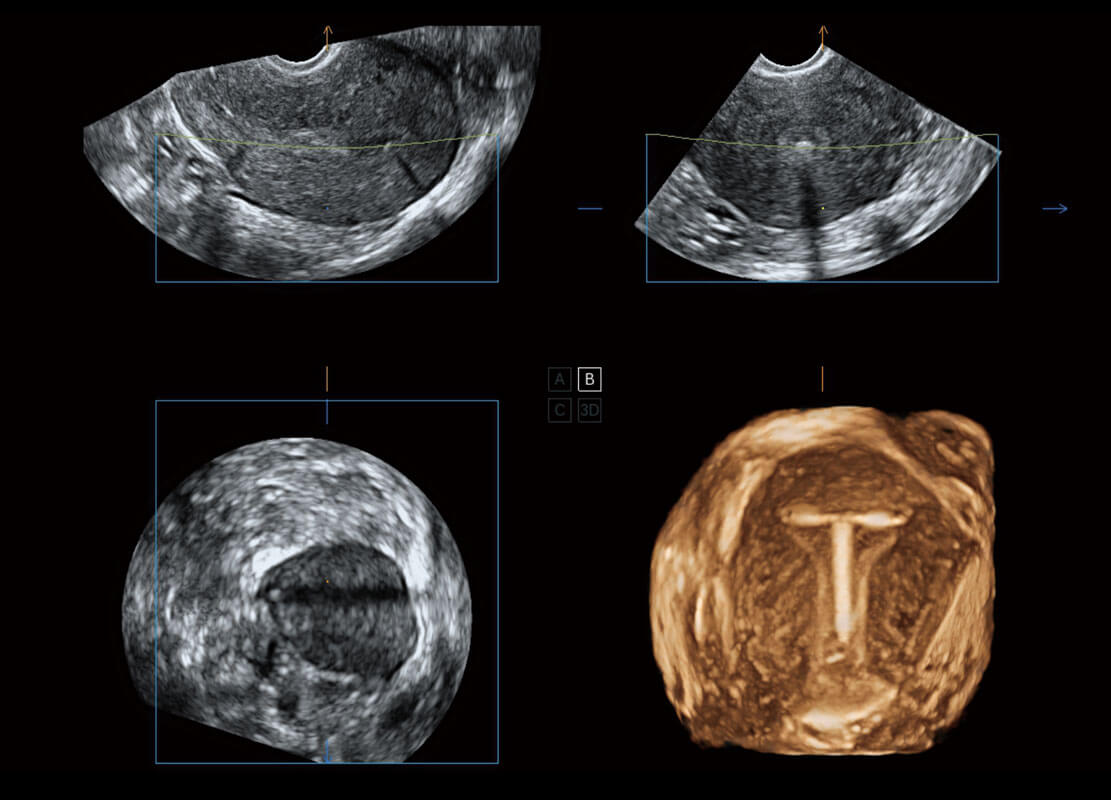

P60為盆底超聲檢查提供應(yīng)用方案,多種腔內(nèi)及腹部容積探頭提供從二維、三維到四維的優(yōu)異圖像品質(zhì),實時快速三維容積數(shù)據(jù)獲取,專業(yè)的測量工具包等人性化設(shè)計,為超聲醫(yī)生診斷提供有力保障。

能夠簡化盆底檢查的操作流程,可在二維模式及三維成像模式下實現(xiàn)一鍵自動提取出標準切面、自動識別當前切面、自動測量,提升盆底檢查的高效性,同時也能讓青年醫(yī)生快捷的獲得準確的檢查結(jié)果。